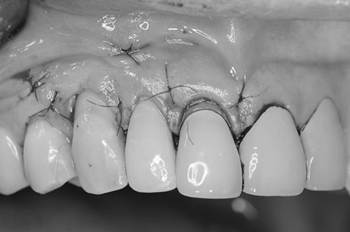

治療前

赤丸の前歯の腫れとお痛みが取れず,近歯科を受診しましたが、抜歯しないといけないといわれ当院を受診しました。患者さんはできるだけ歯を抜きたくないと強い希望がありました。

審美部位なので切開はマイクロメスで傷が目立たない部位に慎重におこない、縫合は7-0のナイロン糸を使用します。

術直後のレントゲンです。